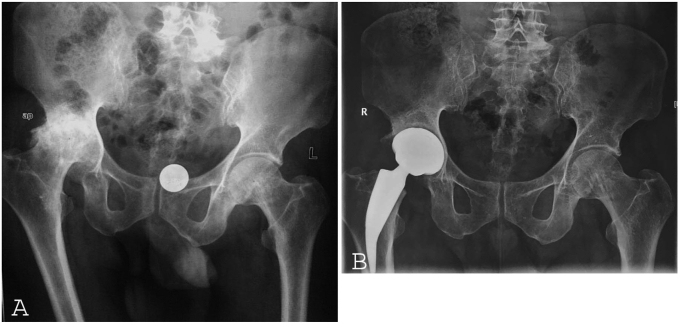

Currently available literature shows good results with cementless total hip arthroplasty in tubercular arthritis of the hip.18, 19, 20, 21, 22 The authors have no preference on the choice of articulation; however, we prefer a ceramic-on-ceramic articulation in younger patients and ceramic on polyethylene for elderly patients (Fig. 1 A & B).

Fig. 1.

Radiograph of pelvis with both hips in Anteroposterior view showing post-tubercular arthritis of right hip in a 24-year-old patient. The patient underwent cementless total hip arthroplasty with modern porous metal cup and short femoral neck preserving stem and Ceramic on Ceramic articulation (A) Post-operative follow up radiograph of pelvis with both hips showing stable total hip arthroplasty prosthesis in situ at 4 years follow up (B).